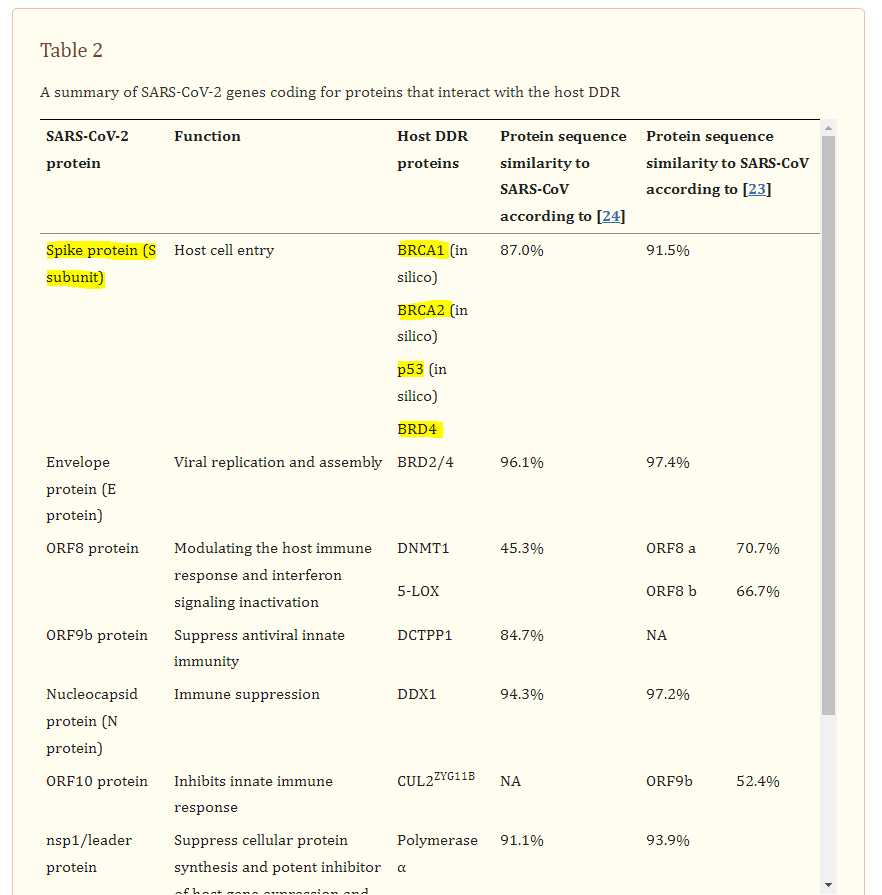

From the review “The consequences of viral infection on host DNA damage response: a focus on SARS-CoVs” by Mekawy et al (2022)1:

BRD2/4 interactions with SARS-CoV-2 E and spike proteins:

The SARS-CoV-2 envelope (E) protein forms an ion channel, and its C-terminus resembles the N-terminus of histone H3. Therefore, similar to H3, it was shown to directly interact with bromodomains (BRDs) (Table (Table2)2) (Fig. (Fig.2A)2A) [24, 51]. In addition to the interaction of the viral E protein with BRDs, the spike protein of SARS-CoV-2 results in enhancement of BRD4 expression, which is a regulator for senescence mechanism. Therefore, high levels of reactive oxygen species (ROS), DNA damage, and cellular senescence were observed in the infected cell lines. Interestingly, treatment of the cells with a BRD4 inhibitor reversed the senescent phenotype [52].

The spike (S) glycoprotein of SARS-CoV-2 undergoes proteolytic cleavage at the S1/S2 site by host furin or furin-like proteases [79]. This cleavage results in the surface subunit S1, responsible for the virus attachment to the host cell surface receptor, and the transmembrane subunit S2, which derives the fusion of the viral and host membranes and allows the release of the viral genome into host cells [80]. The interaction of the S2 subunit with p53, BRCA1, and BRCA2 was predicted in silico (Table (Table2)2) (Fig. (Fig.3D)3D) [48]. BRCA1, BRCA2, and p53 are well-known tumor suppressor proteins. BRCA proteins participate in HR to repair DNA DSBs. BRCA1 functions upstream of BRCA2 in response to DNA damage, while BRCA2 plays a main role in the regulation of RAD51 activity in HR machinery [81]. BRCA1 was previously associated with Tat-dependent transcription enhancement of the HIV-1 infection [82]. Moreover, numerous functional activities of BRCA1 are antagonized by interacting with oncogenic HPV E6 and E7 proteins [83]. Further studies are required to confirm the interaction of the proteins in vitro and also to understand the extent of DNA damage caused by this interaction if confirmed.